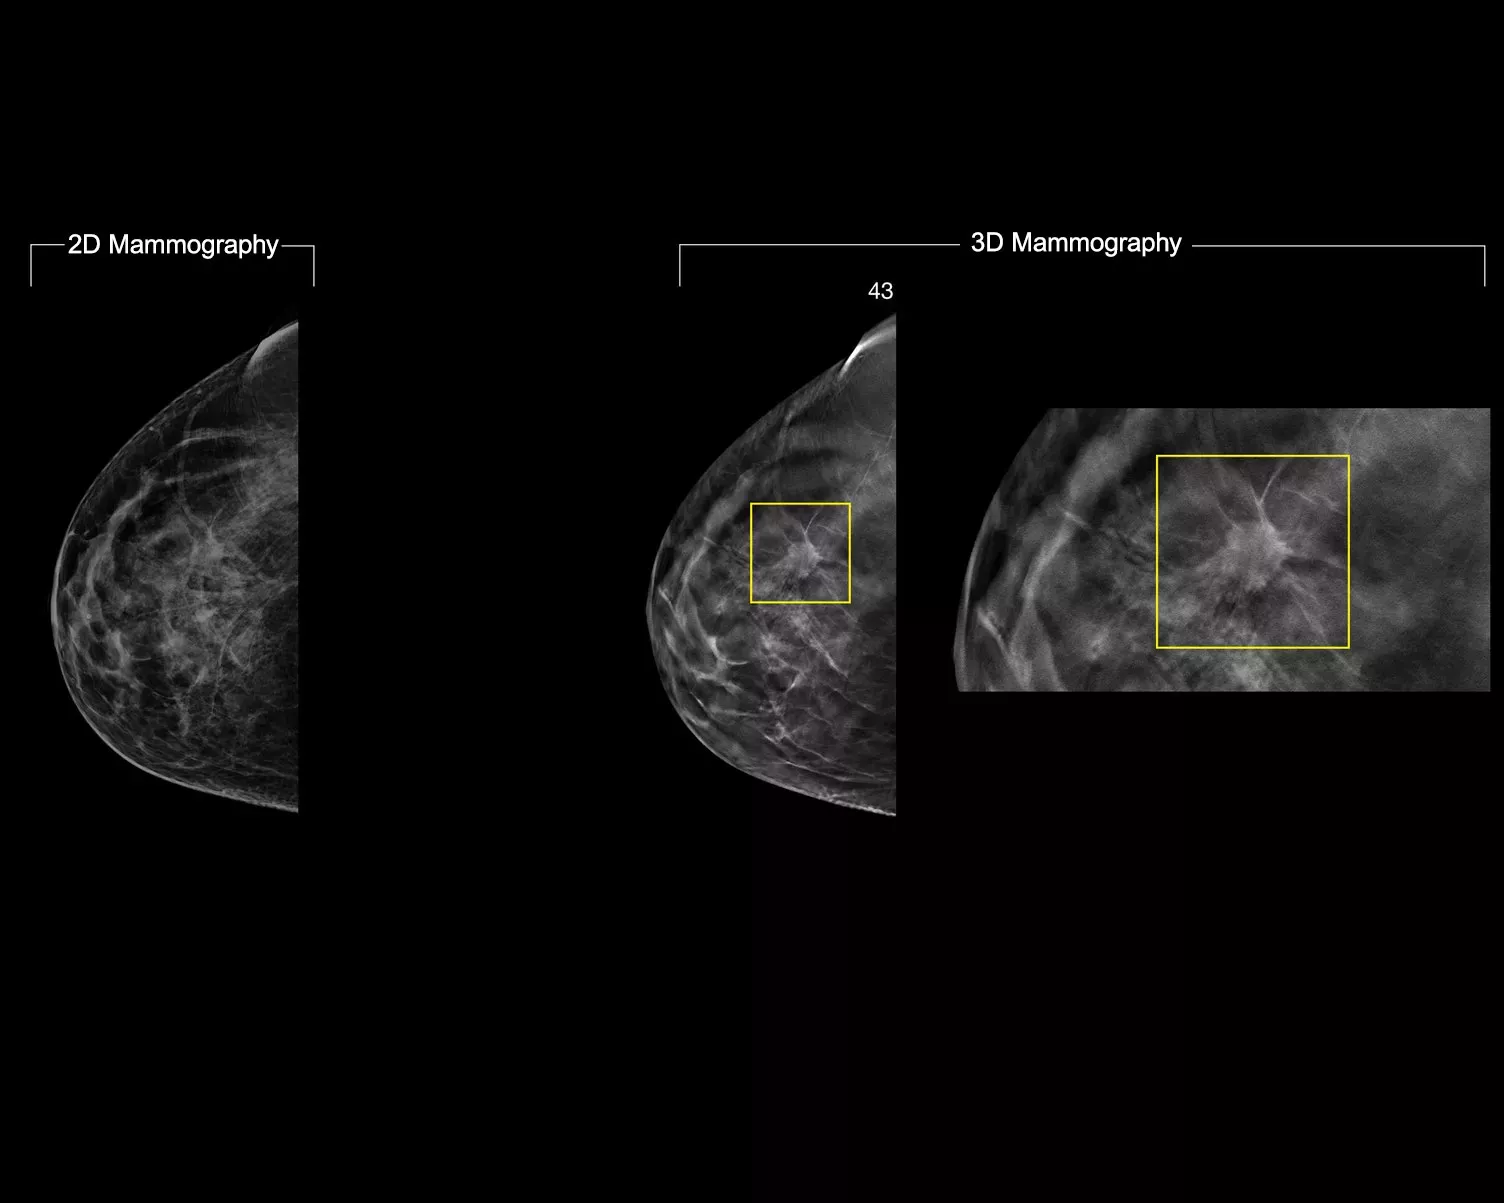

In a constantly changing clinical mammography environment, the flexibility and compatibility of ImageChecker 2D CAD Technology provides detection for conventional 2D images, as well as C-View™ and Intelligent 2D™ synthesised images derived from a tomosynthesis dataset.

ImageChecker 2D CAD Technology searches digital mammograms for potential microcalcifications and masses, characteristics commonly associated with breast cancer.

• Regions-of-interest are highlighted for the radiologist’s attention

• Delivers highly sensitive results without excessive false-positive marks, streamlining case review2

• Easy navigation to the slice of interest in the tomosynthesis stack, when used in combination with Smart Mapping on synthesized 2D images

Digital mammography with peer emphasize marks